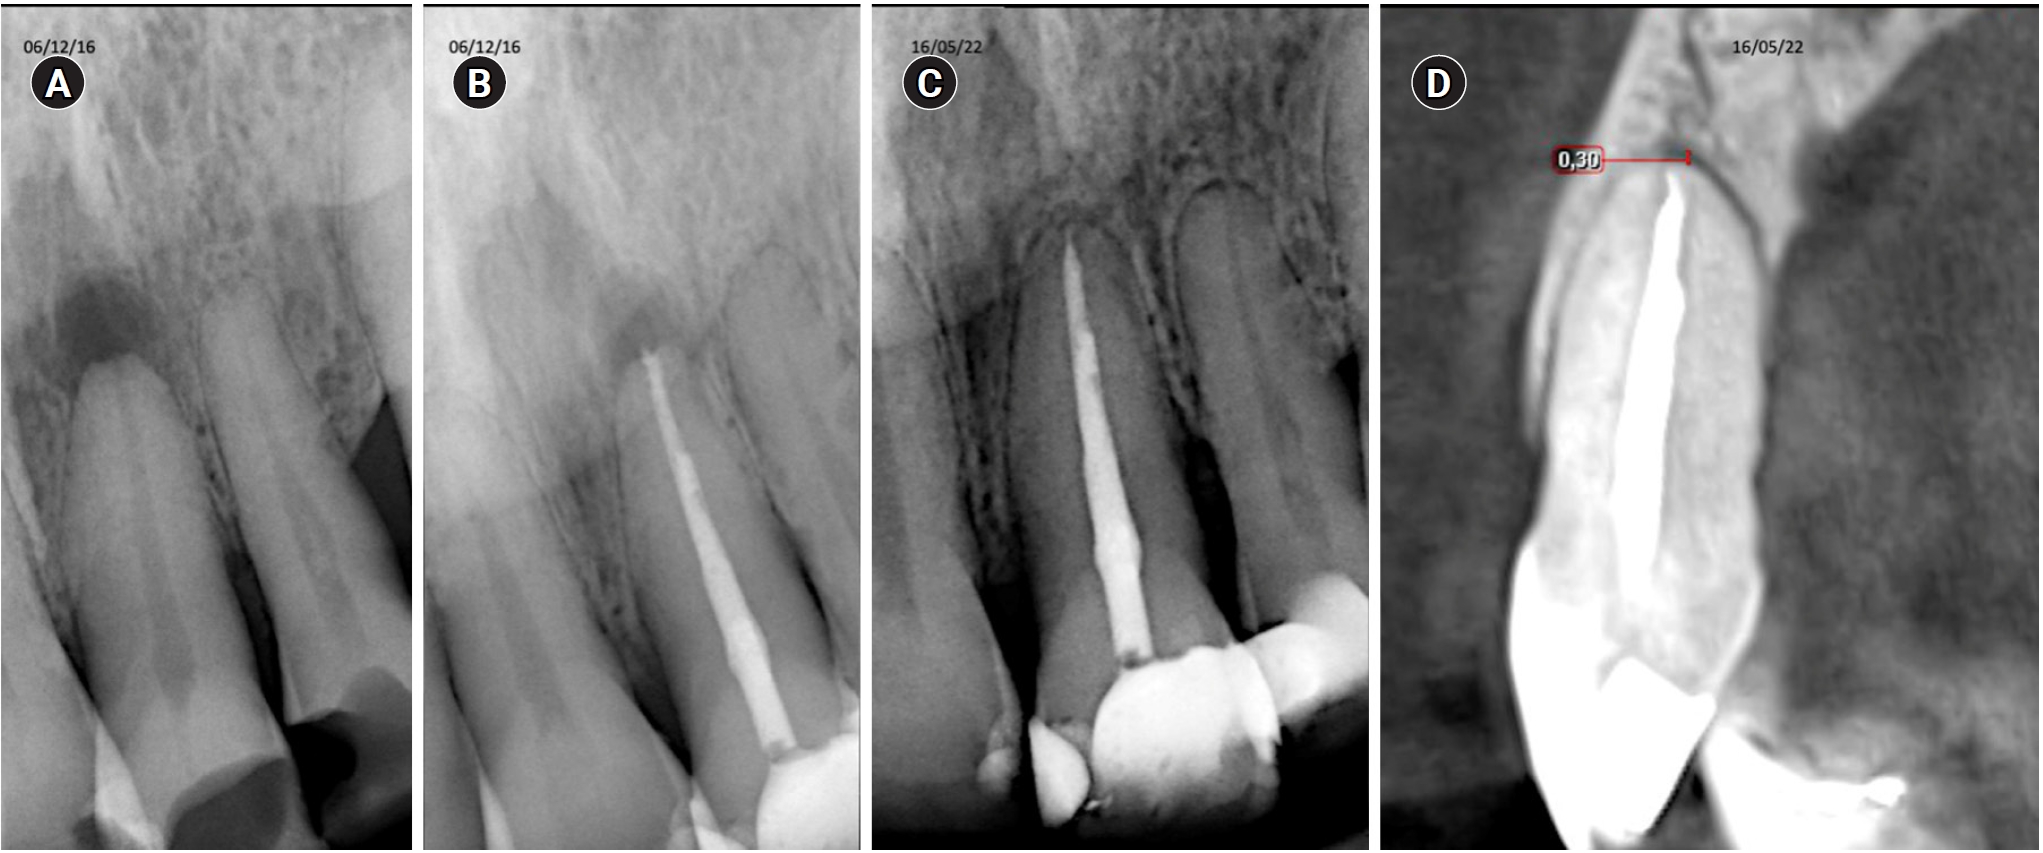

This image shows tooth 11 diagnosed with pulp necrosis with an asymptomatic apical periodontitis. (A) Diagnostic X-ray. (B) Immediate after obturation. (C) X-ray control. (D) Tomographic control where complete healing is evident after 65 months.

Tooth 36 with a diagnosis of pulp necrosis with symptomatic apical periodontitis. (A) Diagnostic X-ray. (B) Immediate after obturation. (C) Radiographic control. (D) Tomographic control after 35 months, showing the apical lesion in the same manner as in the initial X-ray, considered a failure.